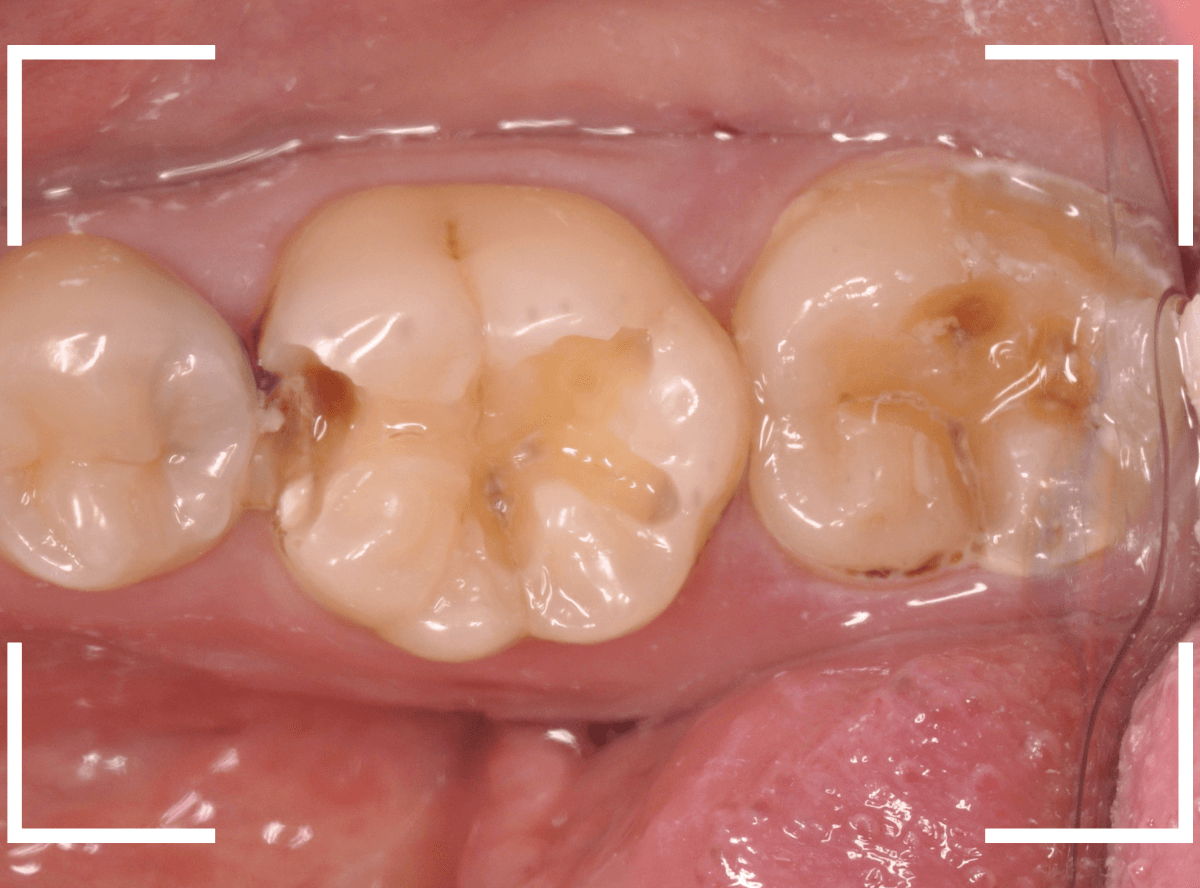

Case.26 4歯連続したセラミック・インレー

4本連続して歯と歯の間の虫歯を治療した患者さんのケースです。

虫歯を再発させないためには、歯と歯のすき間を物がつまらないよう、精密に再製する必要があります。

患者さんのご希望により、セラミック・インレーで修復する事になりました。

最終setした状態です。

左側の大臼歯2本が、ジルコニア・インレー

右側の小臼歯2本が、E-MAX・インレー

になります。

見た目にほとんど遜色ない仕上がりにできました。

普段あまりしない、4歯連続のインレー治療でしたが、精密に仕上げ・setする事が出来てホッとしました。